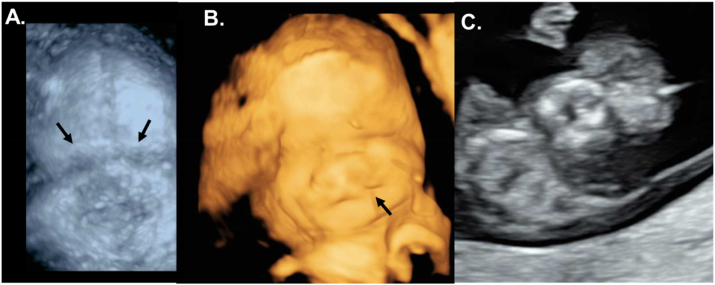

Case presentation: Here, we present a child's case diagnosed with bilateral anophthalmia at 33 weeks of gestation. The newborn was delivered vaginally with a RAX-gene-linked syndrome. Besides craniofacial malformations (bilateral anophthalmia, craniofacial hypoplasia, bilateral cleft lip), the female child had severe endocrine dysfunction (congenital hypopituitarism and diabetes insipidus) postnatal that required specialised monitoring and clinical management. Our case study reports a novel homozygous autosomal recessive non-sense mutation (c.106G>T; p.Glu36Ter) of the RAX gene. This is the first description of this pathogenic gene variant in the literature.

Conclusions: Early and precise sonography is crucial in detecting these conditions on time to prepare postpartum care and avoid delays in optimal clinical treatment for the affected child. This case report aims to raise the scientific community's awareness about this rare genetic syndrome, showing an individualised two-year follow-up program that could help guide physicians and future parents of affected children.